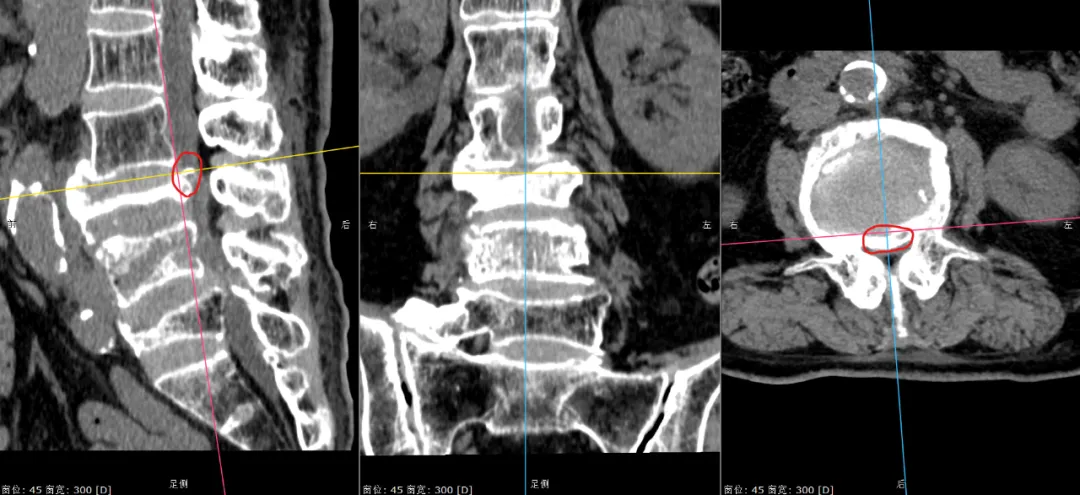

经过检查发现,老人严重骨质疏松,同时连续三个腰椎骨折,神经严重受压,患者不全瘫痪,入院时屈髋、伸膝不能,双下肢仅能勉强抬离床面5-10cm,更别说站立了。

▲张奶奶的三处腰椎骨折(标红处为骨折内巨大空腔、标绿处为陈旧性骨折、标黄处为受压到极限的马尾神经)。

▲张奶奶的神经受压处1(红圈内为压迫神经的骨块)。